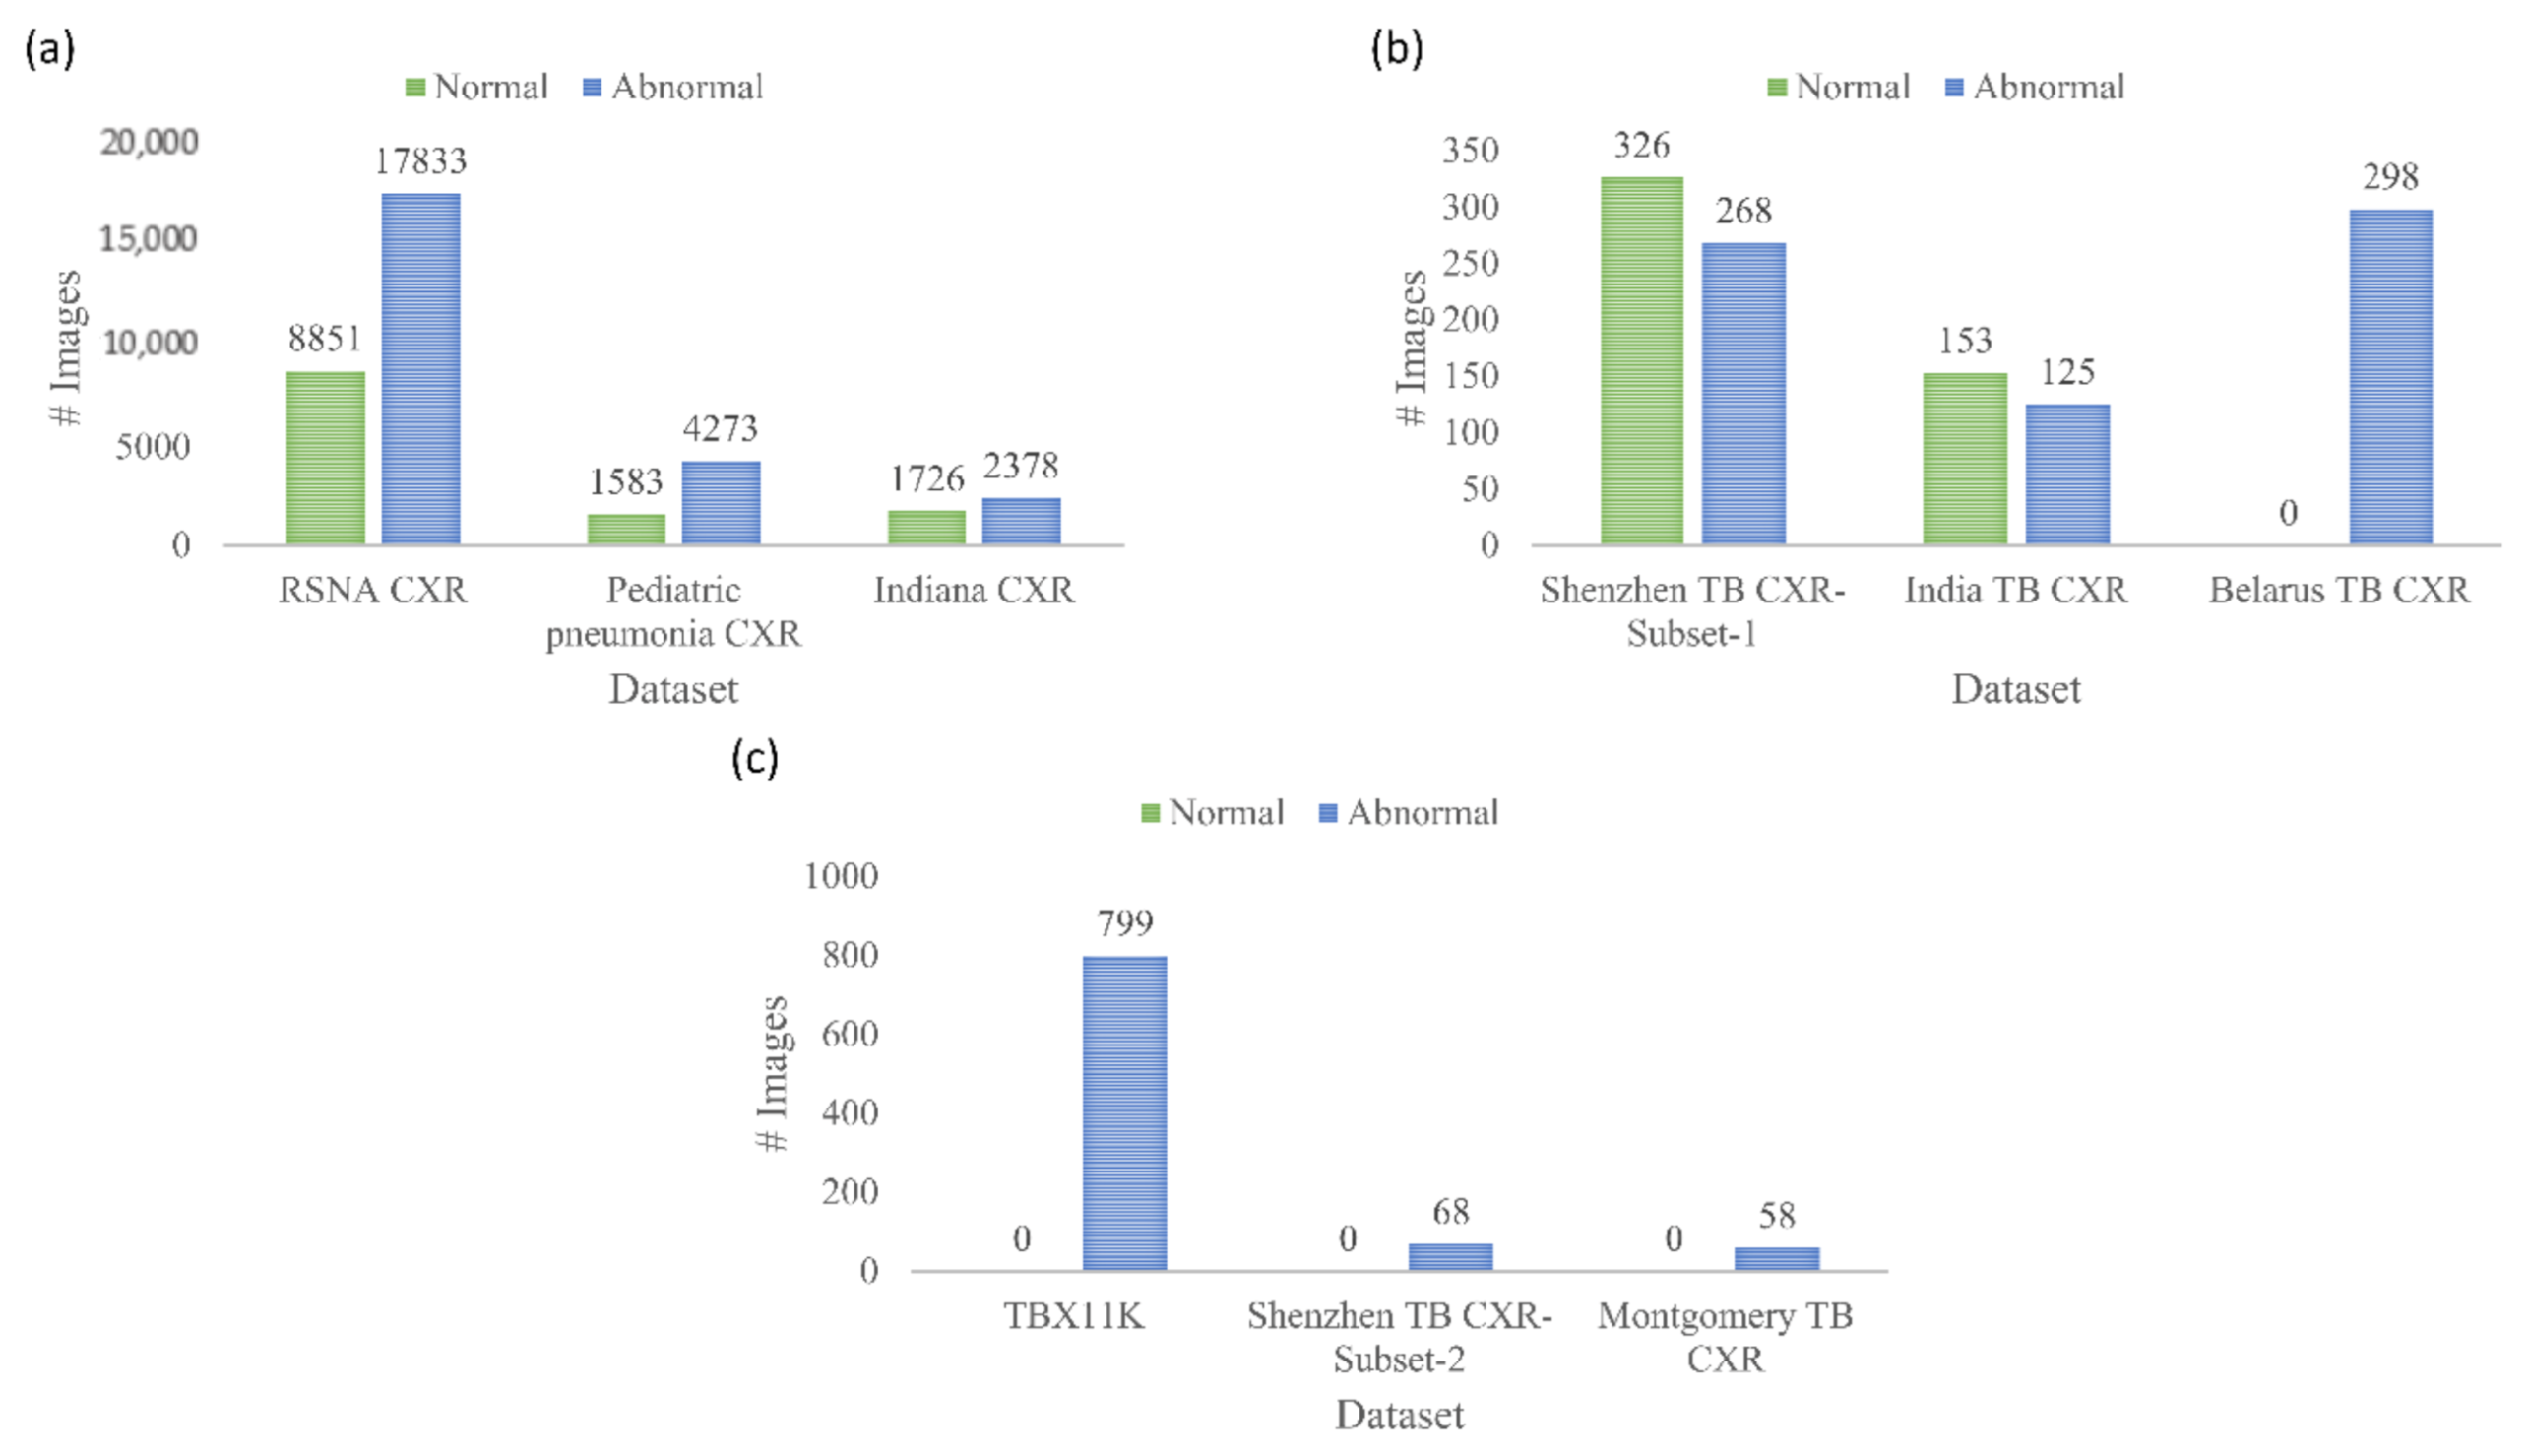

The following publicly available CXR collections are used in this retrospective research study:

(i) Shenzhen TB CXR: This de-identified dataset contains 326 CXRs showing normal lungs and 336 abnormal CXRs showing various TB manifestations [

6]. The CXRs are collected from Shenzhen No. 3 hospital in Shenzhen, China. Each image is tested with diagnostic microbiology gold standard and acquired as a part of routine clinical care. It is exempted from institutional review board (IRB) review (OHSRP #5357) by the National Institutes of Health (NIH) Office of Human Research Protection Programs (OHSRP) and made publicly available by the National Library of Medicine (NLM). In this study, we split this dataset into two: (i) Shenzhen TB CXR-Subset-1 consists of 326 CXRs showing normal lungs and 268 CXRs showing pulmonary TB manifestations. This dataset is used to fine-tune the CXR modality-specific pretrained DL models to classify CXRs as showing normal lungs or TB manifestations. (ii) Shenzhen TB CXR-Subset-2 consists of 68 abnormal CXRs showing pulmonary TB manifestations. This dataset is used to perform cross-institutional testing toward TB-consistent ROI segmentation.

(ii) Montgomery TB CXR: This de-identified dataset is collected by the TB control program of the Department of Health and Human Services (HHS), Maryland, USA. The data set is exempted from institutional review board (IRB) review (OHSRP#5357) by the National Institutes of Health (NIH) Office of Human Research Protection Programs (OHSRP) and made publicly available by the NLM [

6]. The collection includes 58 abnormal CXRs showing various TB manifestations and 80 CXRs showing normal lungs. Each image is tested with the diagnostic microbiology gold standard. Radiologist readings are made publicly available as text files. In this study, we used this dataset to perform cross-institutional testing toward TB-consistent ROI segmentation.

(iii) India TB CXR: The authors [

13] from the National Institute of TB and respiratory diseases, New Delhi, India, released two different CXR datasets that are collected using different X-ray machines. Dataset A includes 78 CXRs for each class, showing normal lungs and others with various TB manifestations. These images were obtained with the Diagnox-4050 X-ray machine. Dataset B includes 75 CXRs for each class, showing normal lungs and other TB manifestations, and is acquired using the PRORAD URS X-ray machine with Canon detectors. This dataset is used in this study to fine-tune the CXR modality-specific pretrained DL models to classify CXRs as showing normal lungs or TB manifestations.

(iv) Belarus TB CXR: The International TB portals program at the National Institute of Allergic and Infectious Diseases (NIAID) is a leading scientific resource of annotated CXRs and CT images of TB patients [

9]. The TB portal contains 298 CXRs showing various TB manifestations that are collected from patients in Belarus. This dataset is used to fine-tune the CXR modality-specific pretrained DL models to classify CXRs as showing normal lungs or TB manifestations.

(v) Tuberculosis X-ray (TBX11K) CXR: The authors [

35] have made available a collection of 11,200 CXR images that are categorized into normal (

n = 5000), sick, but not TB (

n = 5000), active TB (

n = 924), latent TB (

n = 212), active and latent TB (

n = 54) and uncertain TB (

n = 10) classes, where

n denotes the total number of CXRs in each class. Each image in the TBX11K collection is tested with diagnostic microbiology and annotated by the radiologists for TB manifestations. The images are de-identified and exempted for review by relevant institutions. The dataset also provides rectangular bounding box regions for TB-positive cases. Note that using bounding boxes instead of fine annotation implicitly introduces errors in the training since a fraction of non-TB pixels are treated as the positive class in pixelwise training. This dataset is used to train and evaluate the U-Net segmentation models toward TB-consistent ROI segmentation.

(vi) Pediatric pneumonia CXR: This collection [

36] includes 1583 anterior-posterior CXRs showing normal lungs and 4273 CXRs showing bacterial and viral pneumonia manifestations. The CXRs are collected from pediatrics of 1 to 5 years of age from the Guangzhou Women and Children’s Medical Center, China. The images are acquired as a part of routine clinical care with IRB approvals. This dataset is used to perform CXR modality-specific pretraining of the ImageNet-pretrained CNN models toward classifying CXRs as showing normal lungs or other abnormal pulmonary manifestations.

(vii) Radiological Society of North America (RSNA) CXR: A part of the NIH CXR collection [

37] is curated by the radiologists from RSNA and Society of Thoracic Radiology (STR) and made publicly available for a Kaggle challenge to detect pneumonia manifestations [

38]. The collection includes 8851 CXRs showing normal lungs, 11,821 CXRs showing other abnormal manifestations, but not pneumonia, and 6012 CXRs showing various pneumonia manifestations. The images are made available in DICOM format at 1024 × 1024-pixel resolutions. Ground truth (GT) disease annotations are made available for the CXRs belonging to the pneumonia class. This dataset is used in this study toward performing CXR modality-specific pretraining. (viii) Indiana CXR: This collection [

39] includes 2378 posterior-anterior CXRs showing abnormal pulmonary manifestations and 1726 CXRs showing normal lungs. These images are collected from various hospitals that are affiliated with the Indiana University School of Medicine. The dataset is de-identified, manually verified, archived at the NLM, and exempted from IRB review (OHSRP # 5357). This dataset is used during the CXR modality-specific pretraining stage. The datasets used in various stages of the proposed study and their distribution are summarized in

Figure 2.